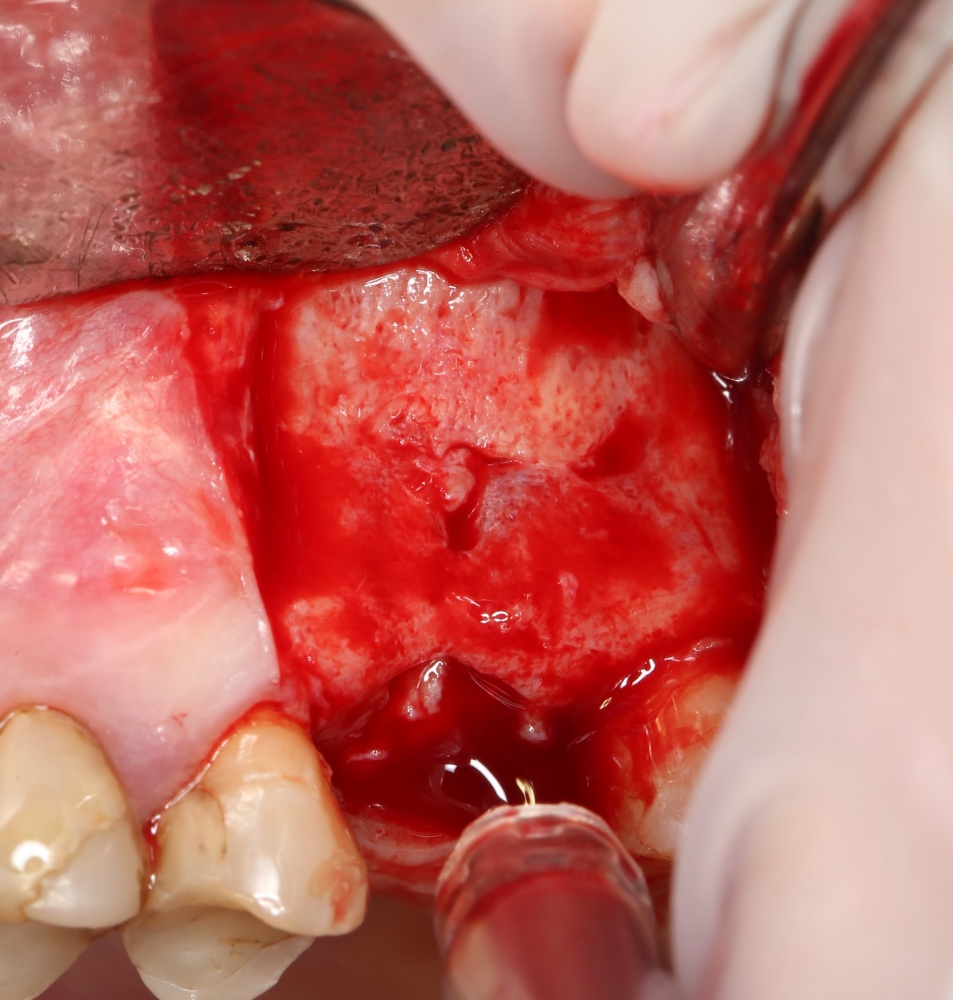

Кстати, обрати внимание на ширину альвеолярного гребня (левая картинка). Она чуть меньше 3 мм. Это объясняет, почему я засомневался в возможности установки имплантатов одновременно с остеопластикой. Понятно и без КЛКТ.

Наперво, мне нужно удалить разрушенный зуб и получить костный аутотрансплантат.

Для получения костного блока, мы открываем донорскую зону, наружную косую линию нижней челюсти.